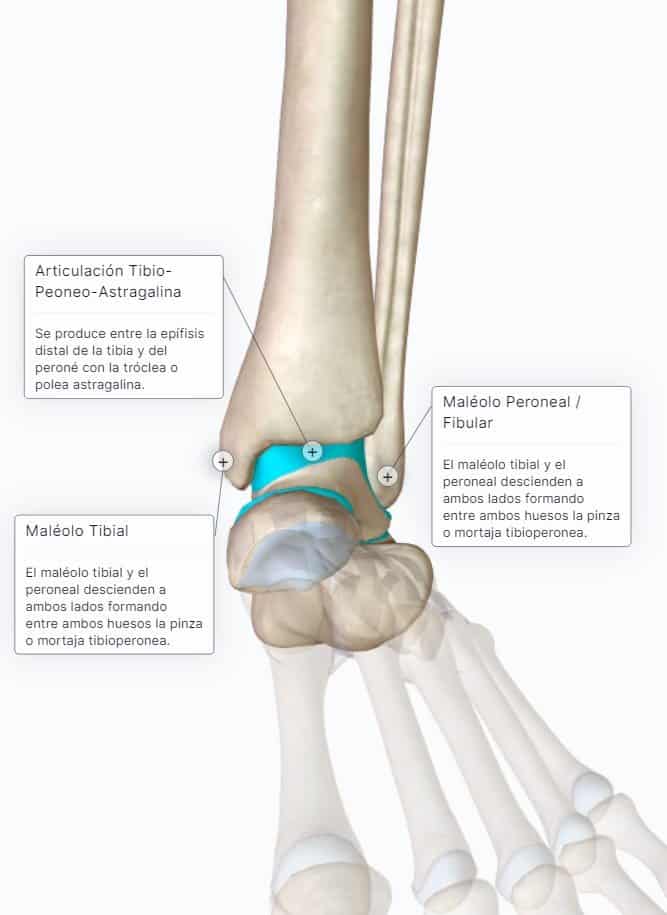

Articulación del Tobillo Anatomía Concise Medical Knowledge Cajon Anterior Del Tobillo La inestabilidad después de los esguinces de tobillo, particularmente los esguinces laterales, se evalúa mediante la prueba del cajón anterior. Las principales pruebas para el tobillo lateral son: La prueba del cajón anterior evalúa esencialmente el ligamento astragaloperoneo anterior y debe realizarse en ligera flexión. La prueba del cajón anterior del tobillo se realiza para evaluar la estabilidad del ligamento. Cajon Anterior Del Tobillo.